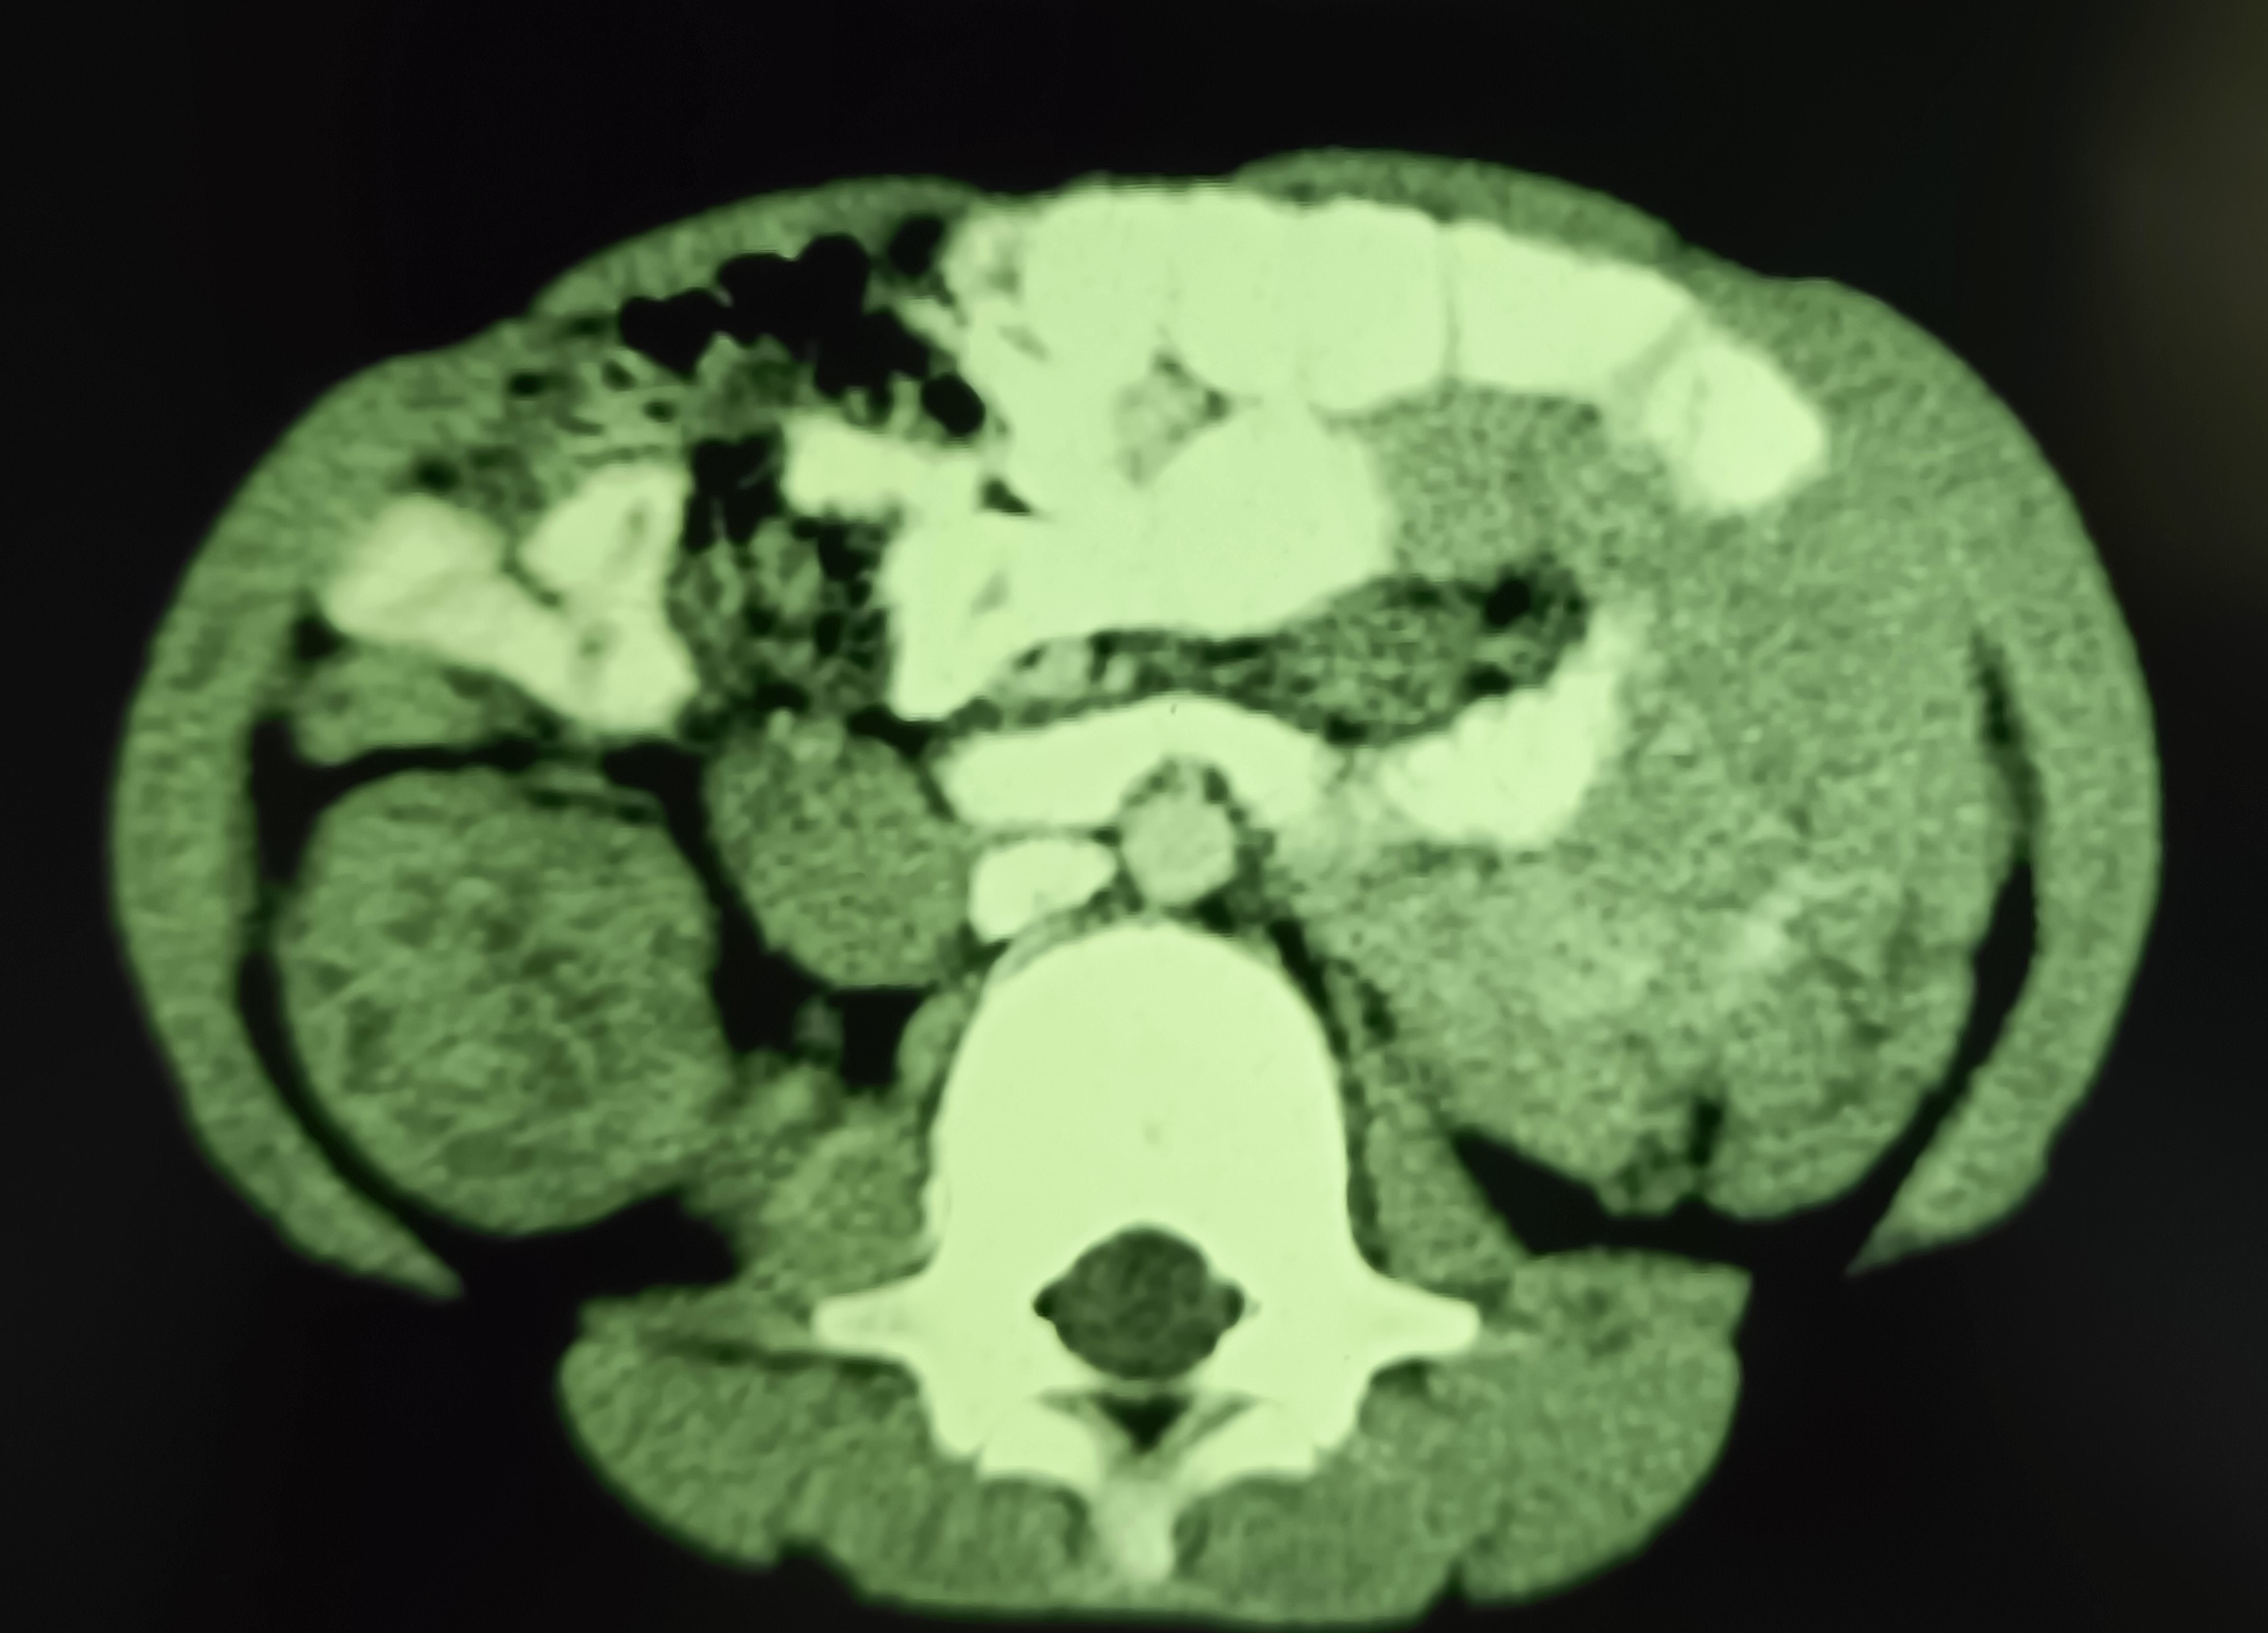

A 7 years old male child admitted with acute abdominal pain showed classic signs of target sign/doughnut sign/pseudo-kidney signs on ultrasound and a mass effect in right iliac fossa on CT. However, the child’s condition improved rapidly and in a few hours he became clinically better and pain free, suggesting spontaneous reduction of the intussusception. Recovered completely on conservative treatment and was not operated.